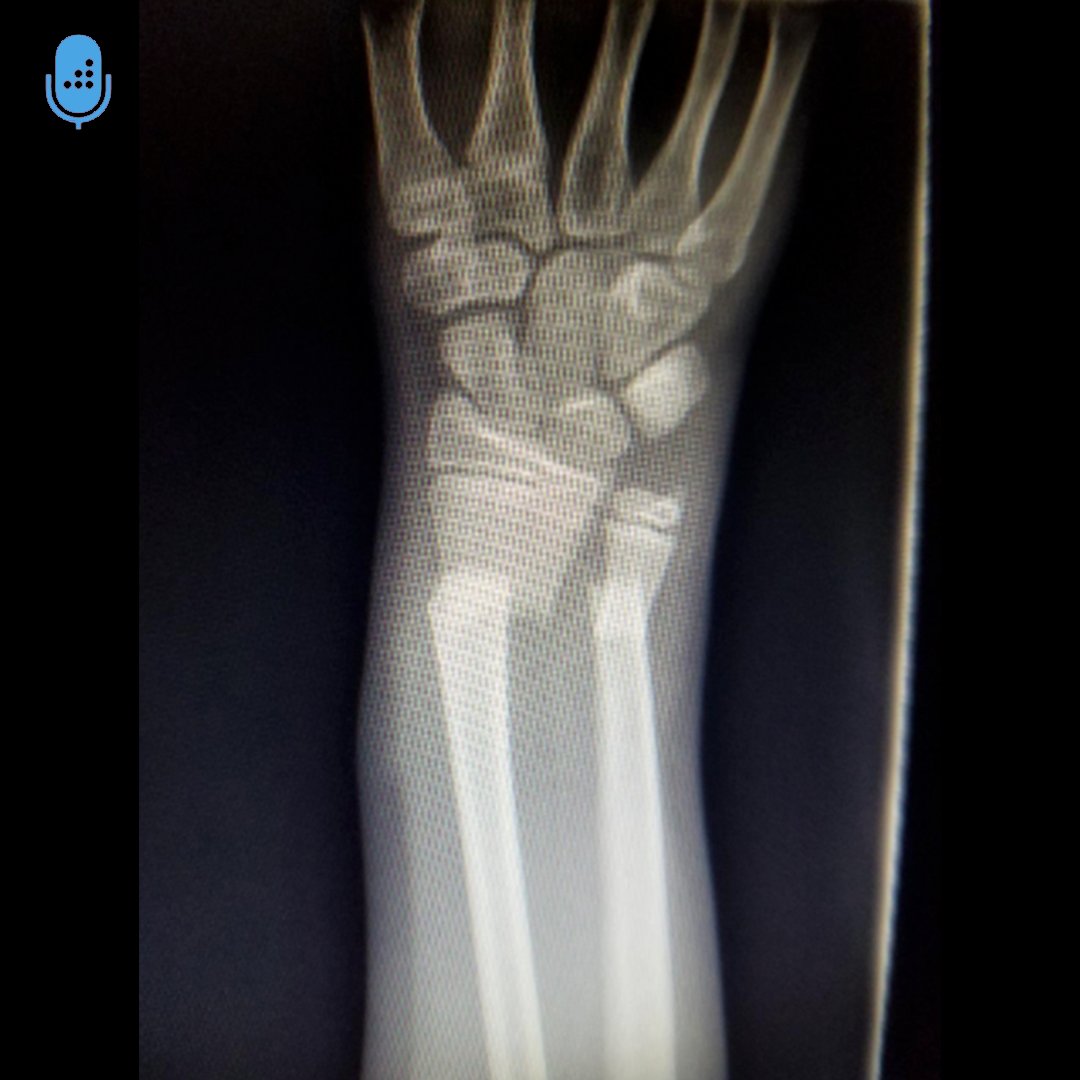

Can you answer this daily question from our Free QBank correctly?

QID: 215626